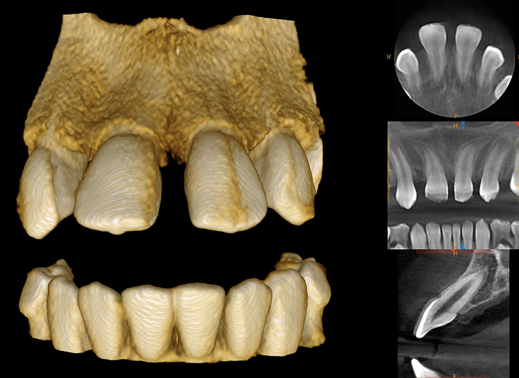

The ultimate in versatility, the CS 9300 system combines dedicated panoramic, optional one-shot cephalometric and up to 7 selectable fields of view cone beam 3D images for the widest range of dental applications.

3D - The innovative CS 9300 delivers crystal-clear, high-quality 3D/CBCT images in seconds. Choose from a variety of fields of view, including Focused, Single/Dual Jaw, TMJ (2x and 4x), Sinus, and Maxillofacial options. The included CS 3D Imaging software enhances treatment planning and facilitates patient communication.

Adjustable Fov - CS 9300 captures a wide range of field of view sizes (5x5, 10x5, 8x8, 10x10 cm) to support a variety of dental applications - from single implants to complete maxillofacial exams.